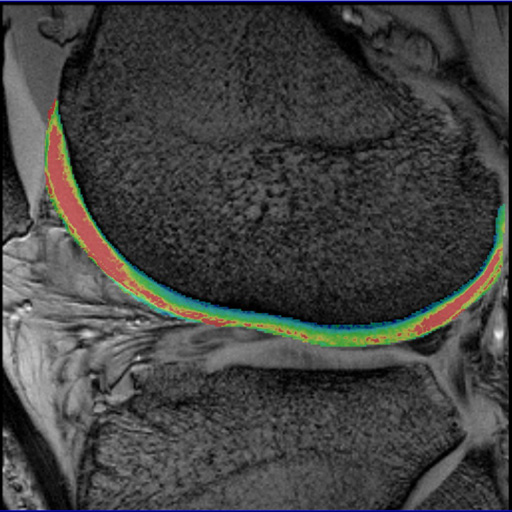

- Syngo MapIt: Provides the protocols and Inline

calculation of parametric maps of T1, T2, and T2* properties

of the imaged tissue. The application range includes

cartilage evaluation of joints, liver, kidney, prostate, and

more.

In particular, syngo MapIt supports the user in detecting

osteoarthritis of the joint based on the T1, T2, and T2*

properties of the cartilage. • 3D VIBE sequence for Inline T1 mapping • Multi-echo spin echo sequence for Inline T2 mapping • Multi-echo gradient echo sequence for Inline T2* mapping • Protocols for fully automated Inline parametric mapping Clinical Applications syngo MapIt allows the early detection of osteoarthritic

pathology based on the T1 and T2 and T2* properties of the

cartilage. Cartilage transplant evaluation It’s possible to use syngo Fusion to overlay these maps with

their corresponding anatomical image

| Knee cartilage seen without syngo MapIt |

Knee cartilage seen with syngo MapIt |

Cartilage visualization at elbow with syngo

| Cartilage visualization at elbow with syngo

MapIt |

syngo MapIt showing patellar cartilage |

syngo MapIt shows degenerative changes of the

femoral cartilage |